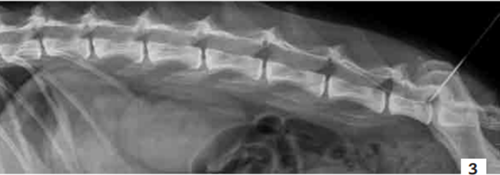

L’apport d’un anesthésique local associé à un morphinique par voie péridurale est envisageable. Il peut se réaliser par l’injection unique d’un mélange de 0,2 ml/kg de bupivacaïne 0,5 % associée à 0,1 mg/kg de morphine dans un volume compris entre 0,2 et 0,26 ml/kg. Le volume maximal ne doit pas dépasser 6 ml. Cette injection unique a une durée d’action estimée à 6 heures [7].

Il est possible d’administrer ce mélange de manière prolongée, aussi longtemps qu’il est jugé nécessaire, en posant un cathéter péridural (photo 3) [21]. La quantité de principe actif à injecter est alors calculée en se fondant sur celle de morphine à administrer. La concentration de la solution de morphine est de 2 mg/ml. La dose nécessaire est de 0,3 mg/kg/24 h. Une fois le volume de morphine calculé, la même quantité de bupivacaïne 0,5 % est ajoutée. Le mélange est alors administré sur 24 heures à l’aide d’un pousse-seringue [9].

Photo 3 - Cliché radiographique de profil de la colonne lombaire d’un chien.

Noter le cathéter péridural qui permet de compléter le protocole analgésique avec un anesthésique local associé à un morphinique par voie péridurale.

Photo : C. Bille